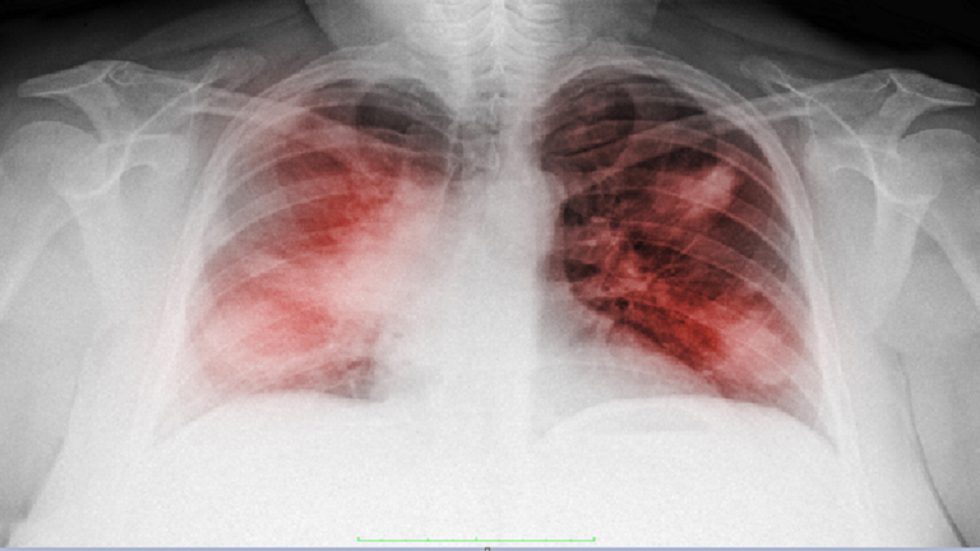

علامات السرطان التي تنسب لأعراض "كوفيد-19"

أعلن إيفان كاراسيف، أخصائي طب وجراحة الأورام، أن أعراض الالتهاب الرئوي عند الإصابة بـ "كوفيد-19" وسرطان الرئة تتطابق جزئيا، لذلك من السهل الخلط بينها.

وقال الأخصائي في حديث لصحيفة "روسيسكايا غازيتا"، لا تظهر أعراض "كوفيد-19" لدى مرضى السرطان بصورة واضحة، لأن المصاب بسرطان الرئة ، يعاني أيضا من السعال والبلغم وصعوبة التنفس.

ما خطورة "كوفيد-19" على مرضى السرطان؟

وأضاف، مرضى السرطان أكثر عرضة من الآخرين لخطر الإصابة بالشكل الحاد من "كوفيد-19"، وخاصة الذين شخصت إصابتهم بالسرطان لأول مرة وكذلك الذين تم علاجهم من سرطان الرئة.

وقال، تشمل المضاعفات الصعبة، التهابا رئويا ثنائي الجانب (يلاحظ في 75% من الحالات)، ومتلازمة الضائقة التنفسية الحادة (17%) و متلازمة خلل وظيفة الأعضاء المتعدد (11%).

وأشار الطبيب، إلى أنه خلال فترة جائحة "كوفيد-19"، يجب على مرضى سرطان الرئة الذين يخضعون للعلاج المستهدف، أو العلاج الشعاعي، التوقف عن العلاج، وأضاف موضحا، يعتبر الهدف الأساسي في هذه المرحلة تخفيض خطر إصابة مرضى السرطان والعاملين بـ "كوفيد-19". وهذا يمكن تحقيقه عن طريق تقليل اختلاط المريض بأقاربه والعاملين في مجال الطب.

المصدر: صحيفة كمسمولسكايا برافدا